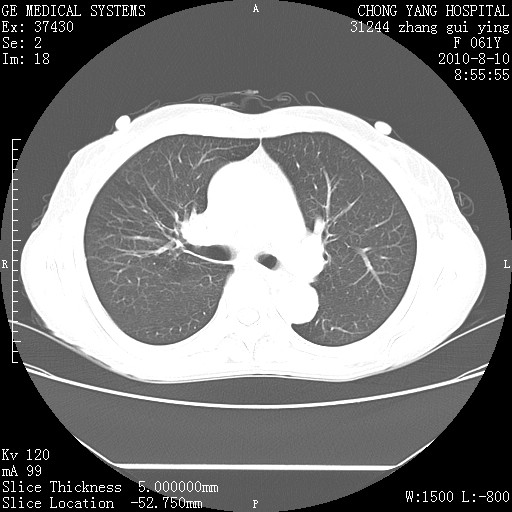

标题: CT28314:F61Y胸部增强,发热咳嗽一周入院,后面的为一周前平 [打印本页]

标题: CT28314:F61Y胸部增强,发热咳嗽一周入院,后面的为一周前平

右肺下叶中心性肺癌可能性大

1、支持考虑右侧中央型肺癌伴右肺中叶节段性不张及下叶支气管黏液痰栓    2、左肺上叶舌段感染。

支持右下肺中央型肺癌并左上肺感染.

我也觉得右肺中叶支气管受累

支持3楼意见,还要考虑:纵隔及肺门淋巴结转移、右侧少量胸腔积液。

确切的说:1:右肺下叶中心型肺癌侵及中叶支气管并中叶不张,纵膈淋巴结转移。2:左肺舌叶炎症。3:右侧胸腔少量积液

1:右肺下叶中心型肺癌侵及中叶支气管并中叶不张,纵膈淋巴结转移。2:左肺舌叶炎症。3:右侧胸腔少量积液。支持!

右肺下叶中心型肺癌侵及中叶支气管并中叶不张,纵膈淋巴结转移。2:左肺舌叶炎症。3:右侧胸腔少量积液